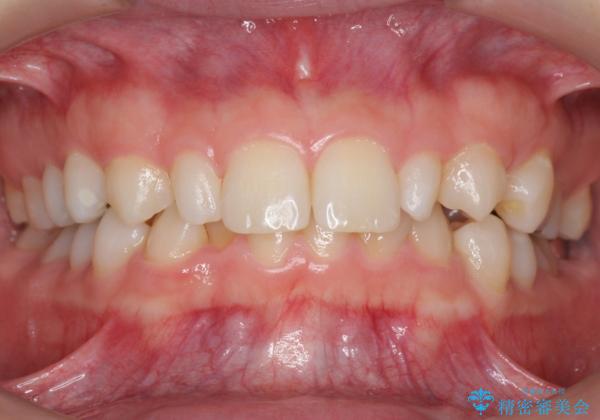

抜歯したスペースを使い、歯並びを整え、さらにその隙間を利用して細い歯を大きく整えてセラミックで被せるという総合的な治療を行いました。

マウスピース矯正→上顎両側2番のセラミック、左下67の虫歯治療 の順で行いました。

矯正治療→ホワイトニング→セラミック の順で行なっています。

ホワイトニングで綺麗に白くした歯に合わせて、被せています。